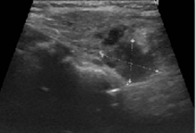

From the study of hypercalcemia with hyperparathyroidism, a cervical ultrasound was performed which confirmed the presence of a nodule suggestive of left parathyroid adenoma (Figure 1) coinciding with the focus of uptake on sestamibi scintigraphy (Figure 2). Primary hyperparathyroidism with hypercalcemia was identified, which could justify the overall clinical picture. The recent worsening of behavioural changes and mental confusion were also interpreted in the same context. A month later, patient underwent left lower parathyroidectomy (Figure 3), and histology revealed parathyroid adenoma (Figure 4).

Figure 4 Main cells arranged in towel and in microfollicles compressing normal parathyroid tissue to the periphery (asterisk) with Chinese ink on the external surface.